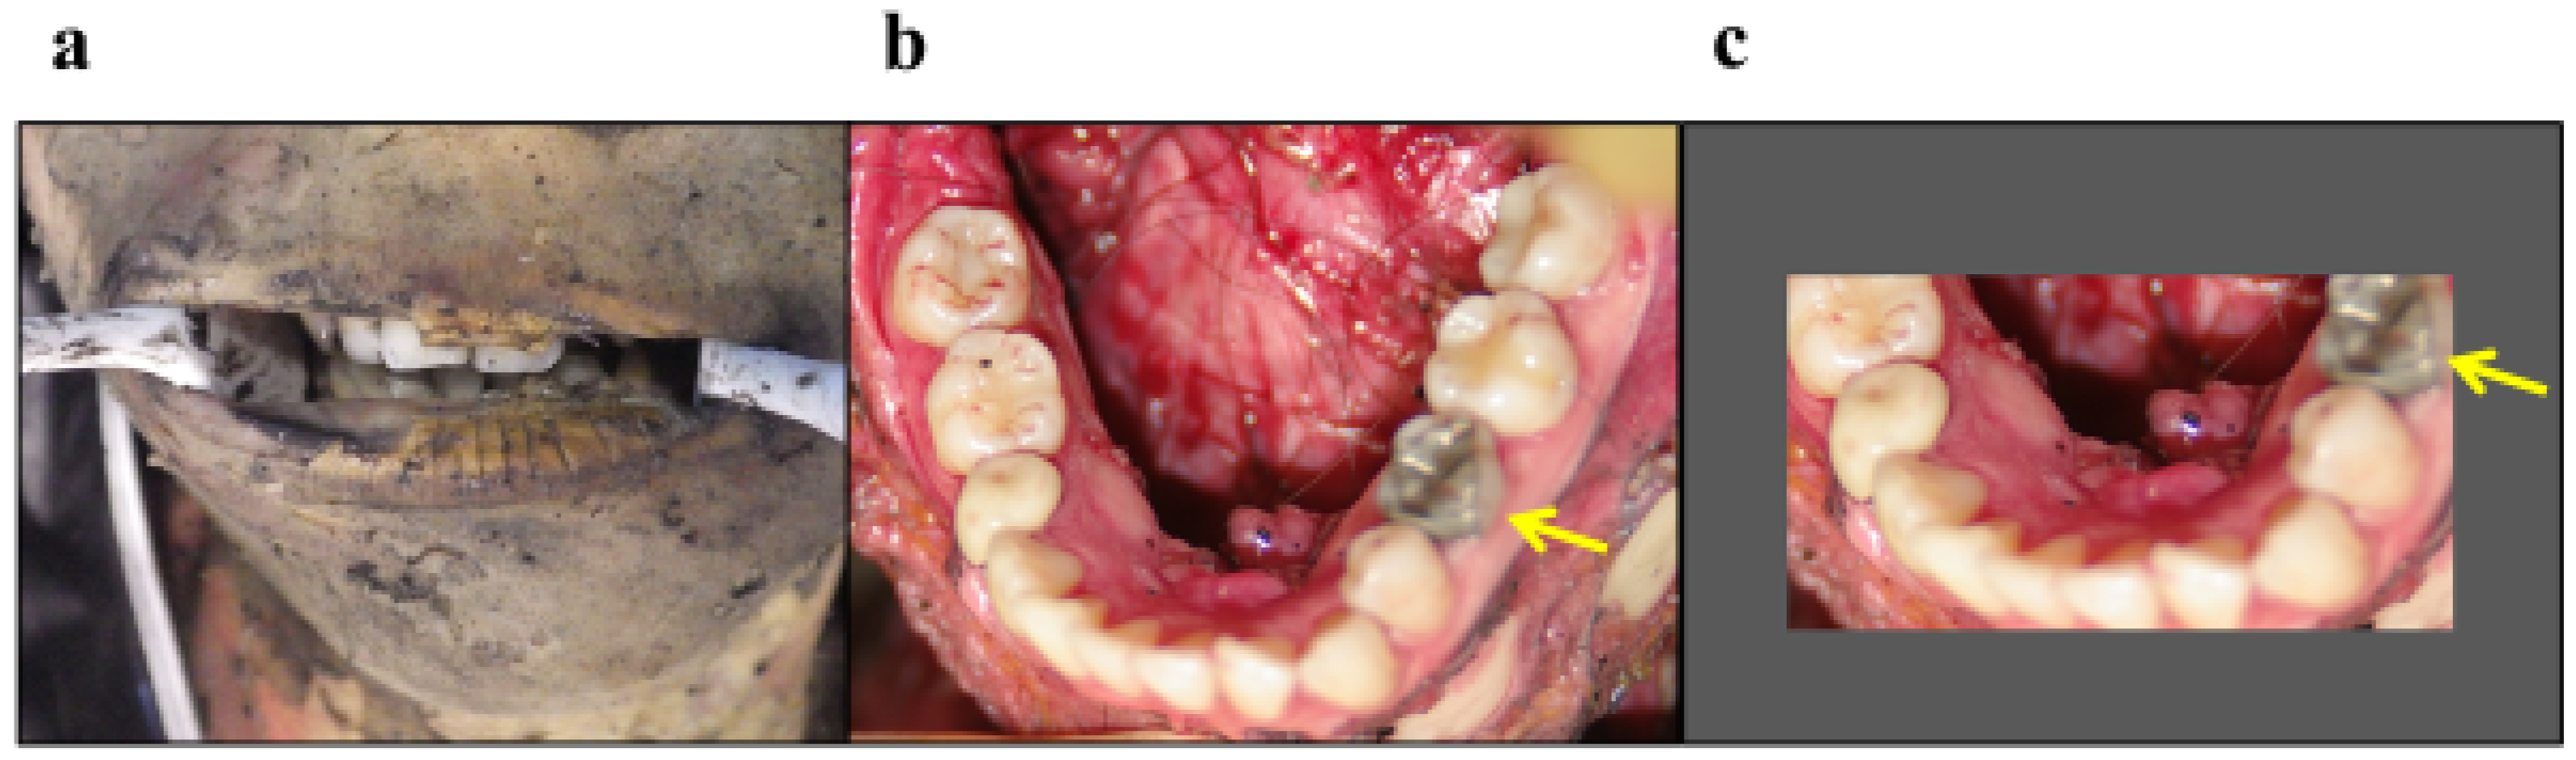

4.3.1. Misidentification of Residual Soot Remaining in a Fissure as Metal Fillings

4.3.2. Cases of Misidentification of Primary Molars as Molars Because of Narrow Opening of the Mouth